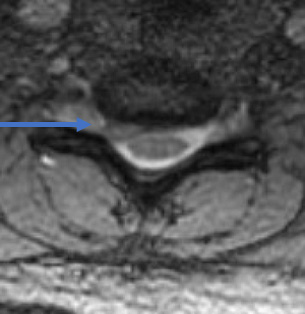

32 year old female comes with right arm pain that radiates all the way down to her fingers. We tried therapy, injections, oral pain medicine, and time. Because of the pain, a MRI showed a herniated disc in her neck on the right side (arrow). The left image is a side view and the right images is a cross section view.

She underwent a minimally invasive anterior cervical discectomy and fusion after removing the herniated disc. A MRI shows resolution of the herniated disc.